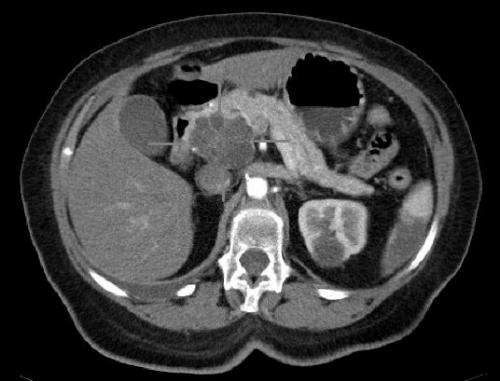

在本研究中,手术中取患者肿瘤样本,并移植到小鼠中以生长成新的胰腺肿瘤。

科学家们首先观察到,与正常胰腺相比,肿瘤中MIR506的水平较低。接下来,他们用MIR506处理实验性肿瘤细胞,以确定它是否以与卵巢癌和其他癌症相同的方式表现。他们发现用MIR506处理胰腺癌细胞抑制了恶性细胞生长以及导致癌症转移的细胞过程。